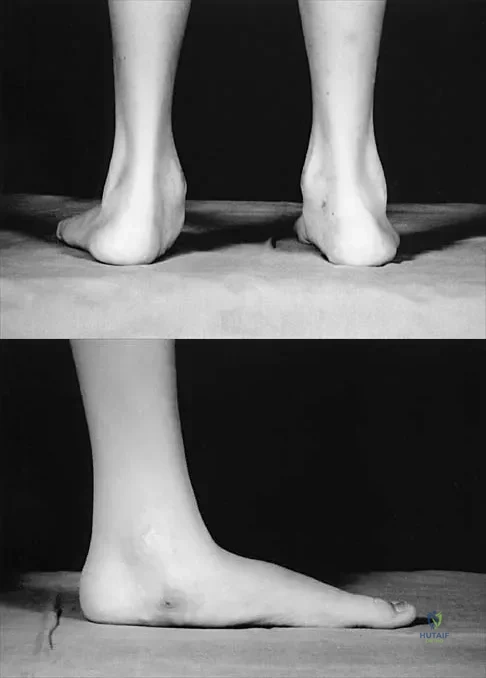

Figures 50a and 50b show the standing clinical photographs of a 12-year-old boy who has had increasing pain in the left foot for the past 9 months. He reports that the pain is activity related, aching in nature, and localized to the medial aspect of the midfoot and hindfoot. History reveals that he sustained a puncture wound located superior and posterior to the medial malleolus from a plate glass window 18 months ago. Examination reveals no restriction of ankle or subtalar motion, normal neurovascular status, no masses, and a well-healed 1.5-cm laceration posterior to the superior aspect of the medial malleolus. Inversion strength of the foot is decreased to grade 3/5. Radiographs of the foot show no bony abnormalities. Treatment should consist of

Explanation